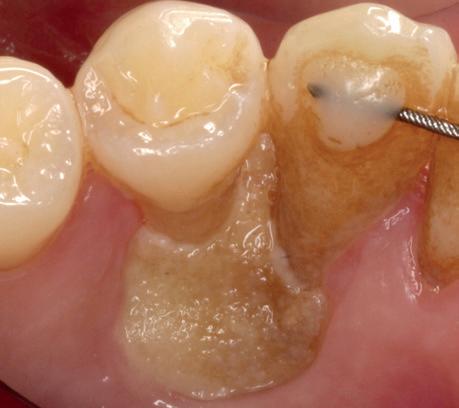

Casus

In deze casus is extractie van de 37 geïndiceerd in verband met een fistel en restpockets, zoals zichtbaar op de röntgenfoto’s (afbeelding 1). Duidelijk te zien is de forse peri-apicale ontsteking en het botverlies bij de 37, dat zowel richting buccaal als linguaal doorloopt. De 37 wordt atraumatisch verwijderd. Er is aan de linguale zijde veel bot verloren en er is sprake van een perforatie aan de buccale zijde.

Er wordt besloten om botmateriaal te plaatsen in de extractie-alveole. Vervolgens wordt het afgesloten met een titanium versterkt d-PTFE membraan (afbeelding 2). Na vier weken wordt het membraan verwijderd.

Zes maanden na extractie wordt het implantaat 37 geplaatst. Er is sprake van een goede genezing en de processushoogte en -breedte zijn behouden en opgebouwd. Ook is er zichtbaar gekeratiniseerd weefsel

1 2 Ridge preservation met d-PTFE membranen 35

gewonnen. De wond kan na het plaatsen van een healing abutment primair gesloten worden (Afbeelding 3a-3d).

In afbeeldingen 4a-c is het resultaat drie maanden na het plaatsen van het implantaat te zien. De genezing is volledig en de verwijzer kan de suprastructuur vervaardigen (afbeelding 4a-4c).

In afbeeldingen 5a-d is de implantaatkroon 37 te zien, twee jaar na plaatsing. Op de röntgenfoto is herstel van zowel corticaal als spongieus bot te zien. (De CB-CT was vervaardigd in verband met implantologische indicatie in het naastliggende gebied).

Deze casus illustreert dat er op een voorspelbare manier een ridge preservation procedure uitgevoerd kan worden met een d-PTFE membraan en er daarna voorspelbaar geïmplanteerd kan worden.